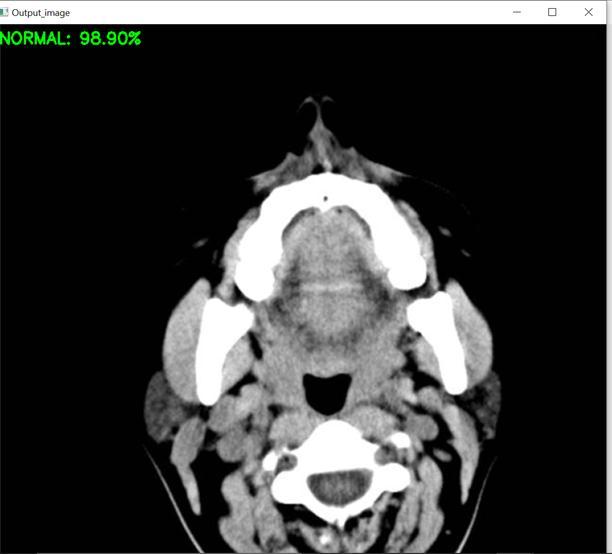

RESULT

TheproposedsystemaccuratelydiagnosestheincidenceofahaemorrhageinthehumanbrainbyutilisingCT scanimages,andtheoutputissuccessfullyachieved.